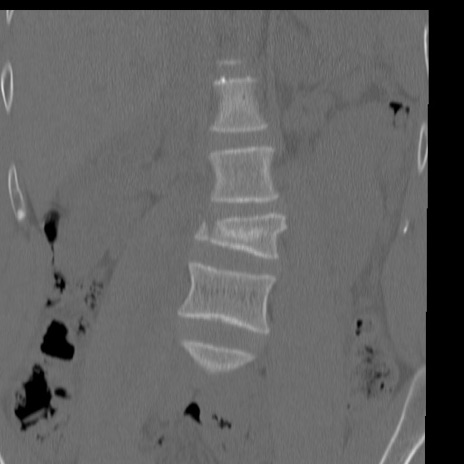

症例3 腰椎CT(冠状断像)

腰椎CT

矢状断像